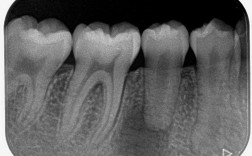

直丝弓技术适用于多种错畸形,包括牙列拥挤、牙列稀疏、深覆合、深覆盖、反合(地包天)、开合及个别牙错位等,其治疗流程通常分为四个阶段:①初诊检查:通过口内检查、X光片(全景片、头颅侧位片)和模型分析,制定个性化方案;②矫治器粘接:将托槽精准粘接于牙齿表面,带环套于后牙;③主动加力阶段:定期更换弓丝(如从细镍钛丝到粗不锈钢丝),施加轻力引导牙齿移动,通常每4-6周复诊一次;④保持阶段:拆除矫治器后,佩戴保持器(如Hawley保持器或透明保持器)维持疗效,防止复发。